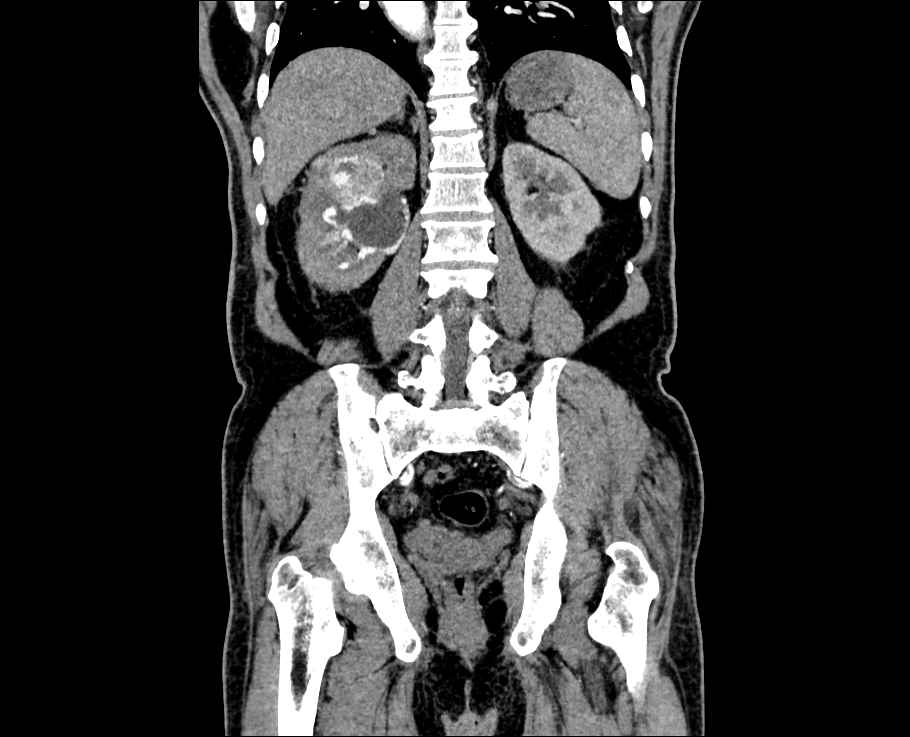

Tumor diameter distribution in patients (n = 285) diagnosed with kidney